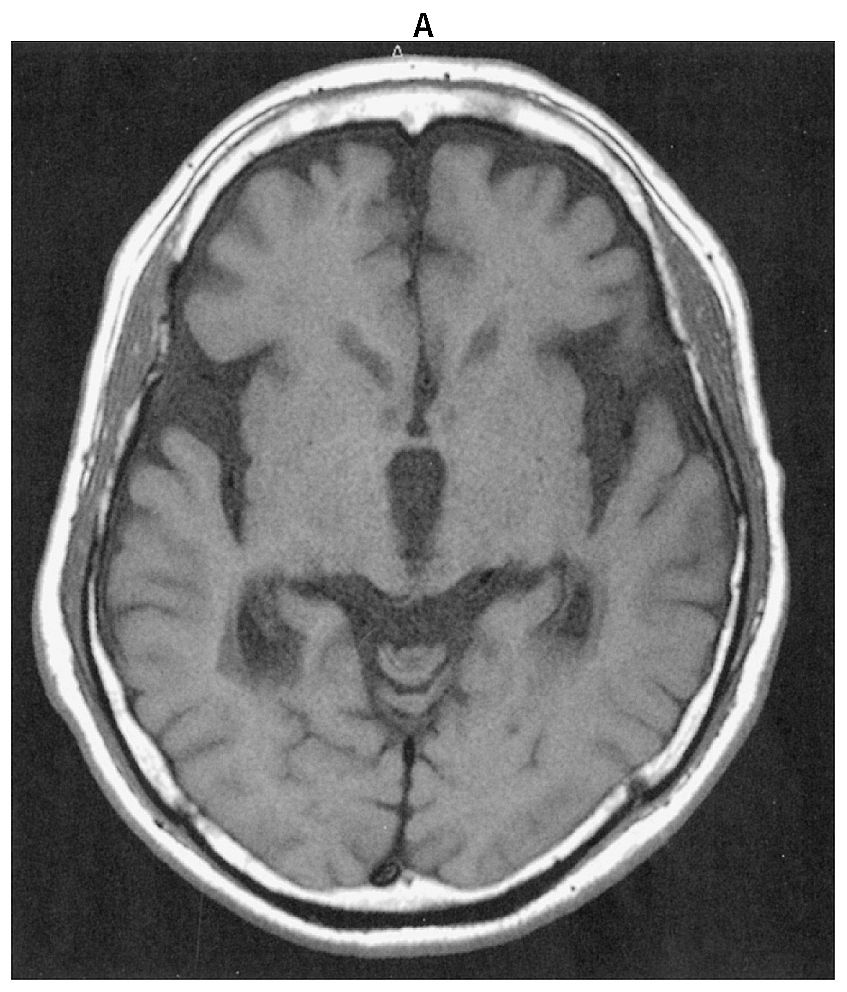

69歳の男性。転びやすいことを主訴に来院した。10年前から糖尿病でインスリン療法を行っている。3年前から歩行時に前のめりになり転倒することが頻回になり,5か月前に左上腕骨を骨折した。診察時,表情は乏しく,やや小声であった。眼球運動は上下方向に制限があり,筋強剛は頸部に強く認めたが四肢では軽かった。四肢の腱反射は正常で,Babinski徴候を認めない。便秘もない。レボドパ〈L-dopa〉の内服による治療効果は認められなかった。頭部単純MRIのT1強調像(A)とドパミントランスポーターSPECT(B)とを下に示す。